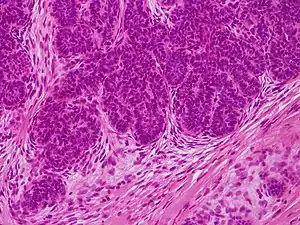

Image at left shows a trichoblastoma from a 68-year-old Caucasian male. It shows a pseudo-encapsulated, multinodular, basaloid tumor with fibrocellular stroma spanning the reticular dermis extending into subcutaneous fat (A). No epidermal connection or retraction artifact was noted. Tumor lobules were arranged as monomorphous basaloid cells in a cribriform pattern with peripheral palisading some resembling abortive hair follicles (B, F). Focally, tumor lobules exhibited squamous eddies, papillary mesenchymal bodies, and a germinative component comprising basaloid cells admixed with distinct pales cells (Zellballen) (C–E, D is an enlargement of boxed area in C).[3]